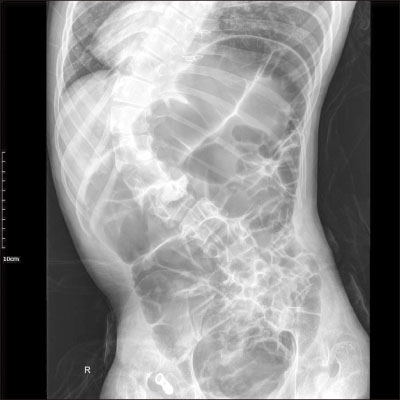

At the time of the current visit, the laboratory values were normal, except for the presence of leukocytosis (13,720/µL) and a C-reactive protein elevation to 1.85 mg/dL. Initial vital signs were stable at the time of the visit to the emergency department. On X-ray imaging, diffuse gaseous distension of colon was seen (

Fig. 2), and right-sided stomach gas was also seen, which was identified as SI at the previous visit to Seoul National University Hospital which was mentioned above.

Fig. 2Diffuse gaseous distension of colon on abdominal X-ray.